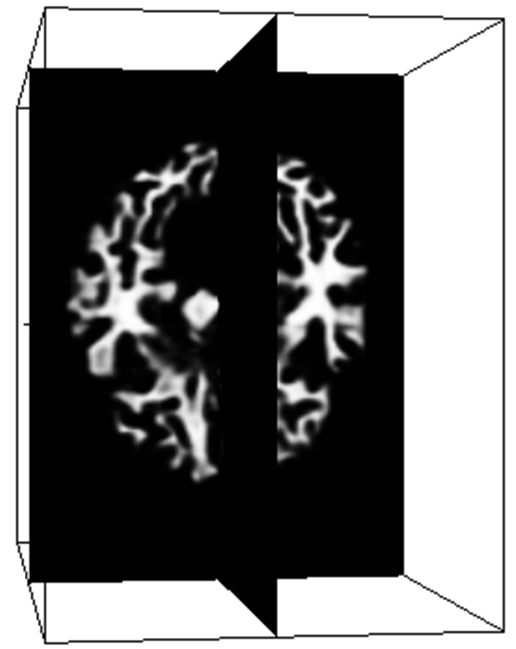

To evaluate the performance of the proposed method, we perform cross-validation on iSeg dataset. Fig. 2 shows the validation results of the proposed method for the ninth subject on different slices. This demonstrates the robustness of the proposed network architecture for accurate segmentation.

Refer to caption

Figure 2: Segmentation result on different slice (a) T1 image, (b) T2 image, (c) DenseVoxNet, (d) our result, (e) manual segmentation